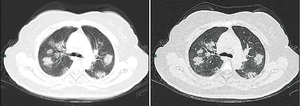

وجدت إحدى الدراسات في الصين أن التصوير الطبقي المحوسب أظهر عتامة الزجاج مغشي في 56 ٪ ، ولكن 18 ٪ لم يكن لديها نتائج إشعاعية. تم قبول 5 ٪ في وحدات العناية المركزة ، و 2.3 ٪ بحاجة إلى دعم التهوية الميكانيكية ، وتوفي 1.4 ٪.[36] عتامات الزجاج المغشي الثنائي والمحيطي هي أكثر نتائج التصوير المقطعي المحوسب النموذجي.[37] التصلد والعتامة الخطية وعلامة الهالة العكسية هم نتائج إشعاعية أخرى.[37] في البداية ، تقتصر الآفات على رئة واحدة ، ولكن مع تقدم المرض ، تظهر المؤشرات في كلا الرئتين في 88٪ مما يسمى "المرضى المتأخرون" في مجموعة الدراسة (المجموعة الفرعية التي كان الوقت بين ظهور الأعراض والتصوير الطبقي المحوسب للصدر 6-12 يومًا).[37]